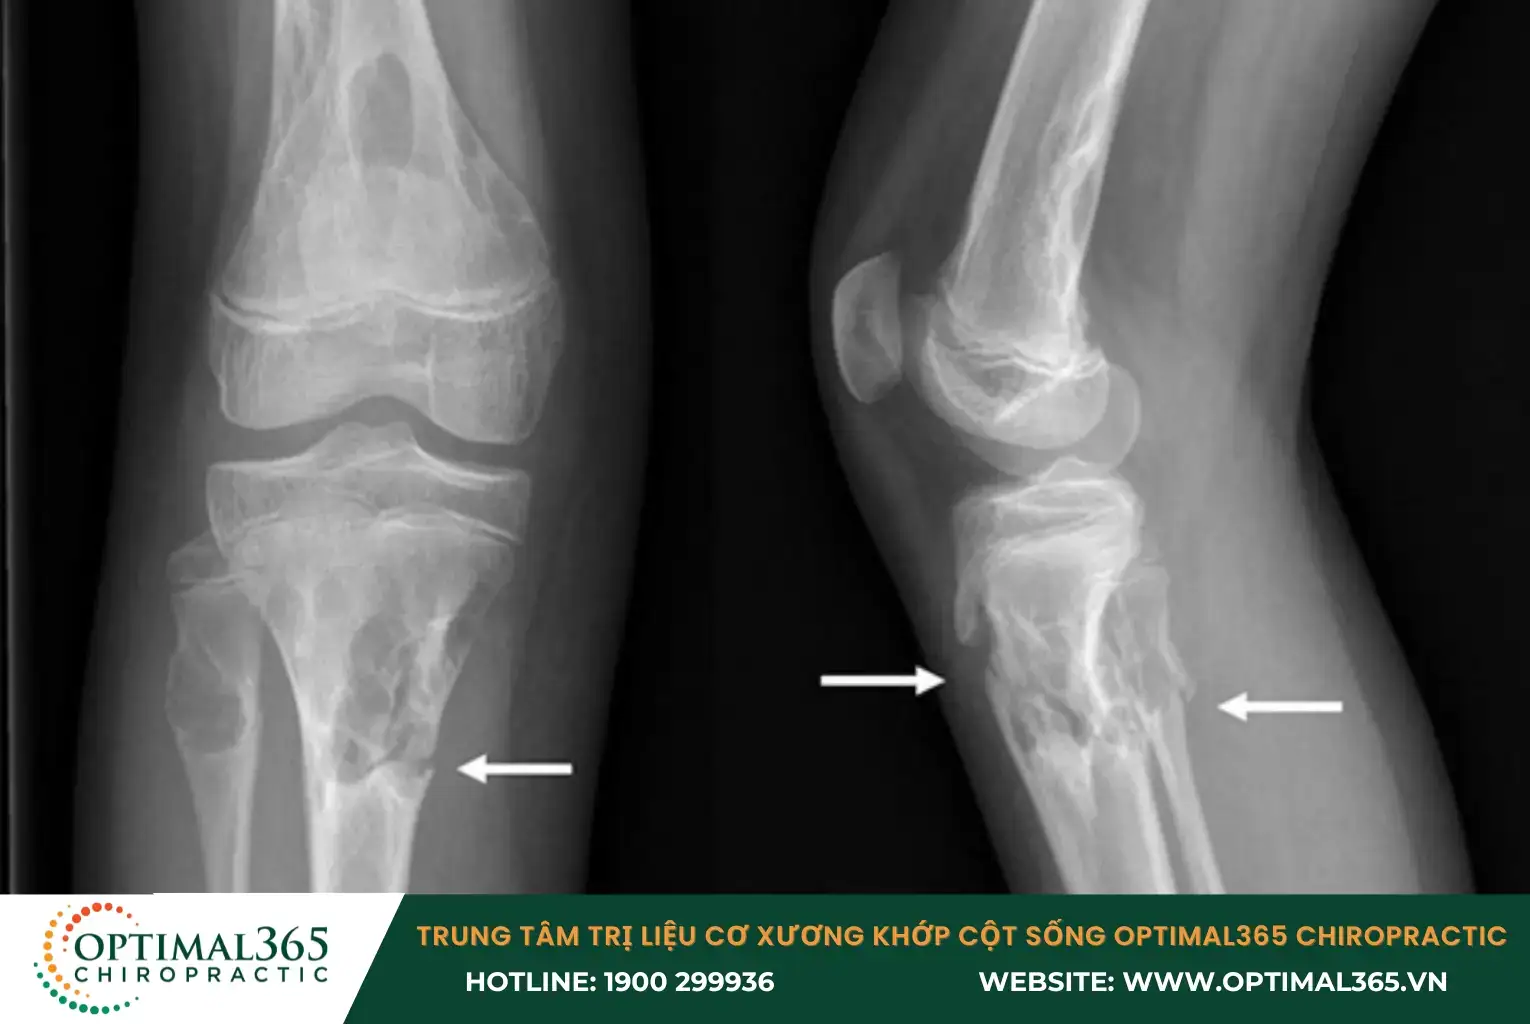

Trước khi tiến hành phẫu thuật tái tạo dây chằng chéo trước, bác sĩ sẽ thực hiện đánh giá kỹ lưỡng tình trạng tổn thương thông qua hình ảnh MRI và kiểm tra lâm sàng. Phẫu thuật này có thể sử dụng các loại vật liệu khác nhau, bao gồm: